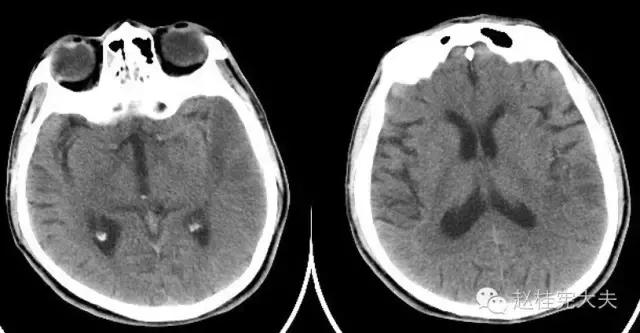

入院前1天的头颅CT:

定位诊断:混合性失语,定位于左侧大脑半球语言中枢(运动和感觉),右侧中枢性面舌瘫,定位于左侧面神经核团以上,右侧上下肢肌力降落,病理征阳性,定位于左侧锥体束。感觉、视野查体无法配合,暂无相应定位考虑。综合考虑,定位于左侧大脑中动脉分布范围。头颅CT:左侧颞叶片状低密度影,左侧大脑中动脉下干支配区,支持临床定位。

定性诊断:结合57岁,男性,急性病程,逐渐加重,进展性右侧肢体无力、混合性失语。头颅CT:左侧颞叶片状低密度影。脑梗死为首先考虑,左侧大脑中动脉支配区,大动脉粥样硬化型。尽管患者本人无高血压、糖尿病等危险因素,但患者母亲有中风、糖尿病史,存在家族中风危险因素,故待完善血生化及血管等卒中危险因素筛查。入院后继续急诊抗血小板、降脂稳定斑块及脑保护治疗。